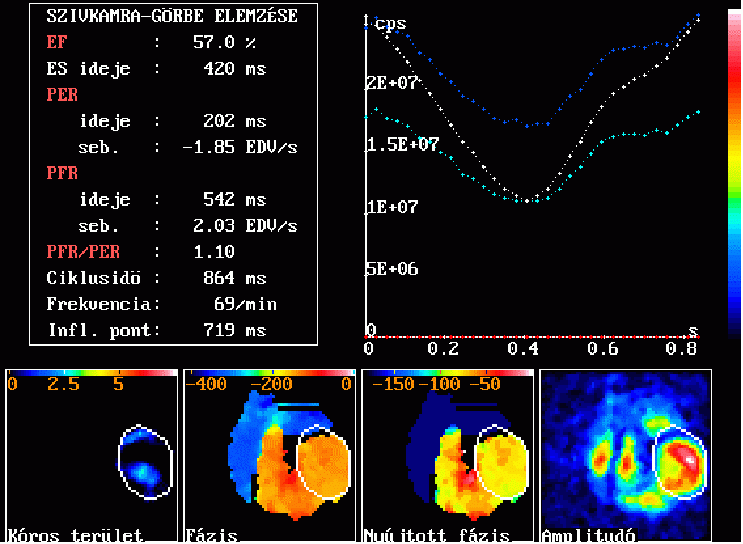

A vörösvértestek „fél” in vitro jelölésével, EKG-kapuzással végzett bal kamrai vértartalom (és ezáltal kamrafal-mozgás) vizsgálat eredményképén jobbra fent egy átlagos szívciklus ideje alatt történő balkamrai aktivitásváltozás normális görbéje látható. Az ebből számított paraméterek a bal oldalon vannak feltüntetve. Az alsó sorban a képelemenként számolt paraméter-értékeket tartalmazó ún. "parametrikus képek" láthatók: